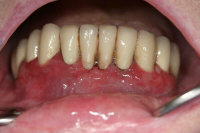

Parodontal stabilitet karakteriseras av framgångsrik behandling genom kontroll av lokala och systemiska riskfaktorer, vilket resulterat i

• minimal blödning vid sondering (BVS < 10 % av tandytorna)

• fickdjup < 3 mm

• ingen progressiv parodontal nedbrytning/vävnadsförlust

• optimal förbättring i övriga kliniska parametrar hos behandlad parodontitpatient.